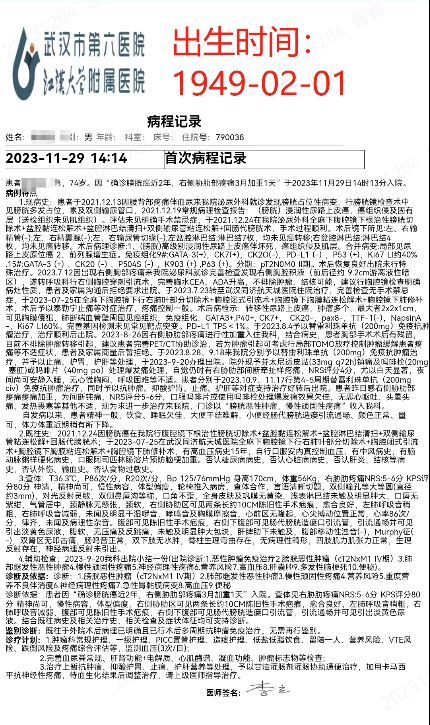

郭某某(BS),男,74岁(出生时间:1949-02-01)

2023-11-29